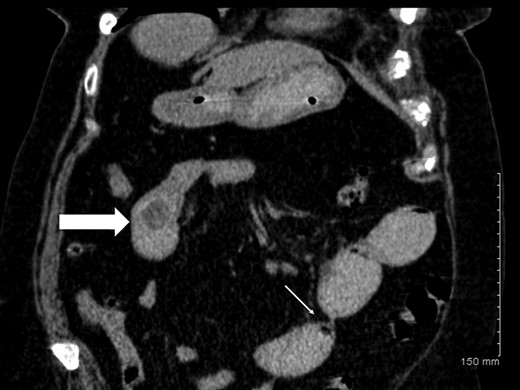

A plain abdominal radiograph was also unrevealing. She proceeded to have computerized tomography (CT) scan of her abdomen and pelvis, which showed dilated small bowel loops consistent with small bowel obstruction. There were two filling defects noted, one in her proximal ileum suspicious for a non-calcified gallstone and the second distally in her terminal ileum (Figs 1 and 2). Appearances were suggestive of gallstone ileus. She was adequately resuscitated and underwent a laparotomy. The small bowel was narrowed in two segments: proximally secondary to an impacted gallstone and an area of stricturing noted distally. Both segments were resected with end-to-end anastomosis performed in a two-layer standard hand-sewn fashion. The clinical impression was one of dual pathology including Crohn's disease and gallstone ileus. She did not undergo a cholecystectomy or repair of her cholecystoduodenal fistula. She made an uneventful post-operative recovery and was discharged home well on Day 7.

Axial CT image demonstrating gallstone in proximal ileum (block arrow) and distal ileal luminal narrowing (thin arrow).

Coronal CT image demonstrating gallstone ileus (block arrow) and stricture in distal ileum (thin arrow).